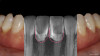

Patient "Jen," age 42, presented with Class III defects (Figure 7) and had previously had a free gingival graft between tooth Nos. 24 and 25. Treatment options were porcelain veneers; porcelain crowns/porcelain bridge after splinting or with removal of tooth Nos. 24 and 25 and pontics; removal of mandibular central mandibular incisors with implant placements (variable placements and restorative options); and composite bonding with or without periodontal splinting.

In doing a DSD blueprint (Figure 8), several questions arose: How would teeth be laid out? If veneers were done, where would they go, and would veneer margins go down into the roots? How would the teeth be prepared? How achievable would insertion be? Would the porcelain veneers have some pink?

Composite bonding was the option chosen. The patient's teeth had some minor mobility, so the practitioner decided to tighten them via orthodontic arch wire splinting to hold them in place. They have done very well and now are not as mobile as before. See in the radiographic analysis where the pink and white is augmented (Figure 9). There were no issues with cleaning. Tissue healing was good. Practitioners must be very diligent about placing the materials and not leaving flash and excess.